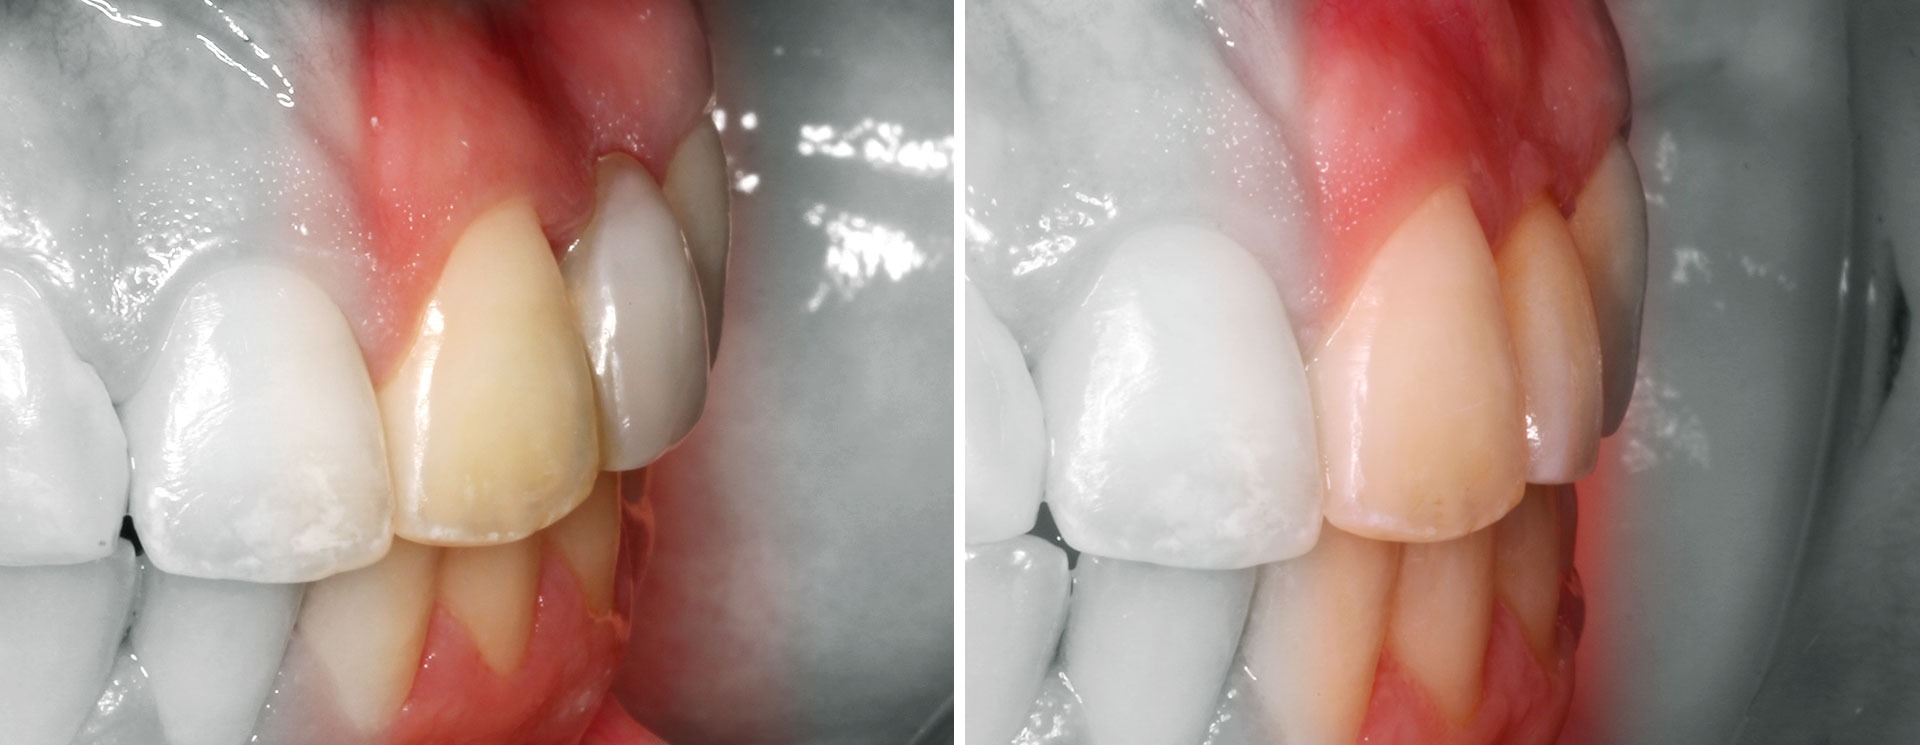

Problemas estéticos